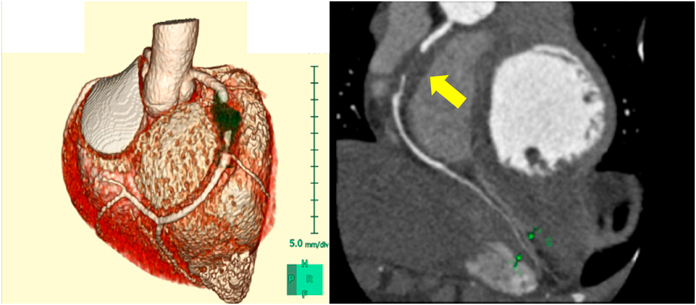

Re-echocardiography in the PICU revealed severe dilatation of the RCA (7.4 mm, Z+9.1) with a low echoic lesion suggesting thrombosis (Fig. 2B) and reduced wall motion in the inferior-posterior area of the LV (Fig. 2A). Echocardiography with two-dimensional speckle tracking (2DST) revealed low radial strain in the inferoseptal and inferior areas (Fig. 2C). Circumferential and longitudinal strain were also low in the same areas. Multi-low detector computed tomography (MDCT) showed occlusion of the RCA at the #2 segment due to thrombus formation with aneurysmatic dilatation of about 2.0 cm in length and 7.0 mm in diameter. The distal segments of the RCA (#3, #4) provided contrast (Fig. 3).

Journal of Pediatric Cardiology and Cardiac Surgery 6(1): 25-30 (2022)

Fig. 3 MDCT showed that the RCA was occluded at the #2 segment due to thrombus formation with aneurysmatic dilatation of 2.0 cm in length and 7.0 mm in diameter (arrow). The distal segments of the RCA (#3, #4) provided contrast

MDCT, multi-low detector computed tomography; RCA, right coronary artery.